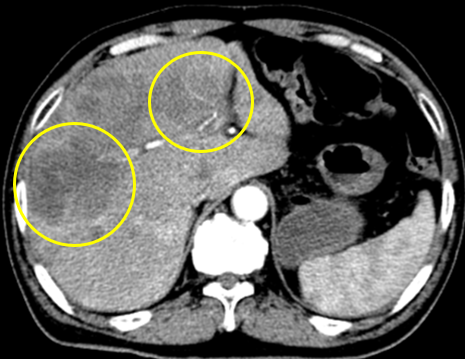

Hình 3: Hình ảnh chụp CT lồng ngực: Nhu mô gan có nhiều khối ngấm thuốc kém, khối lớn nhất kích thước 55x61 mm (vòng tròn vàng)